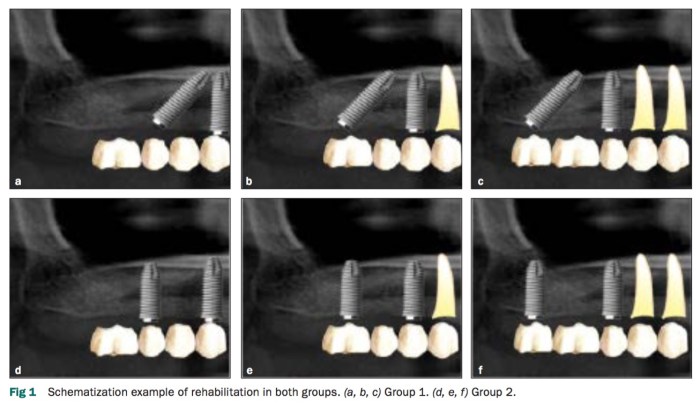

這篇文章是去比較在上顎後牙區,用兩種方式種植兩隻植體,第一種是種兩隻直的,第二種是種一支直的然後另一隻種斜的,然後去追蹤五年的臨床狀況。我覺得厲害的是這個研究團隊可以各組找30位患者,但注意一看,原來是Dr. Malo的團隊,這樣謎題就解開了,只有他真的是會去想種斜的植體,但是他的做法的確有他的理論及實際case report的基礎。

像是這個研究的結果,兩組的存活率幾乎一樣沒有差異,斜的植體反而還有比較少的marginal bone loss(雖然沒有差到很多但有統計上差異). 在種植斜植體已經不是什麼旁門左道的時代,可以在真的compromise的情況下使用。